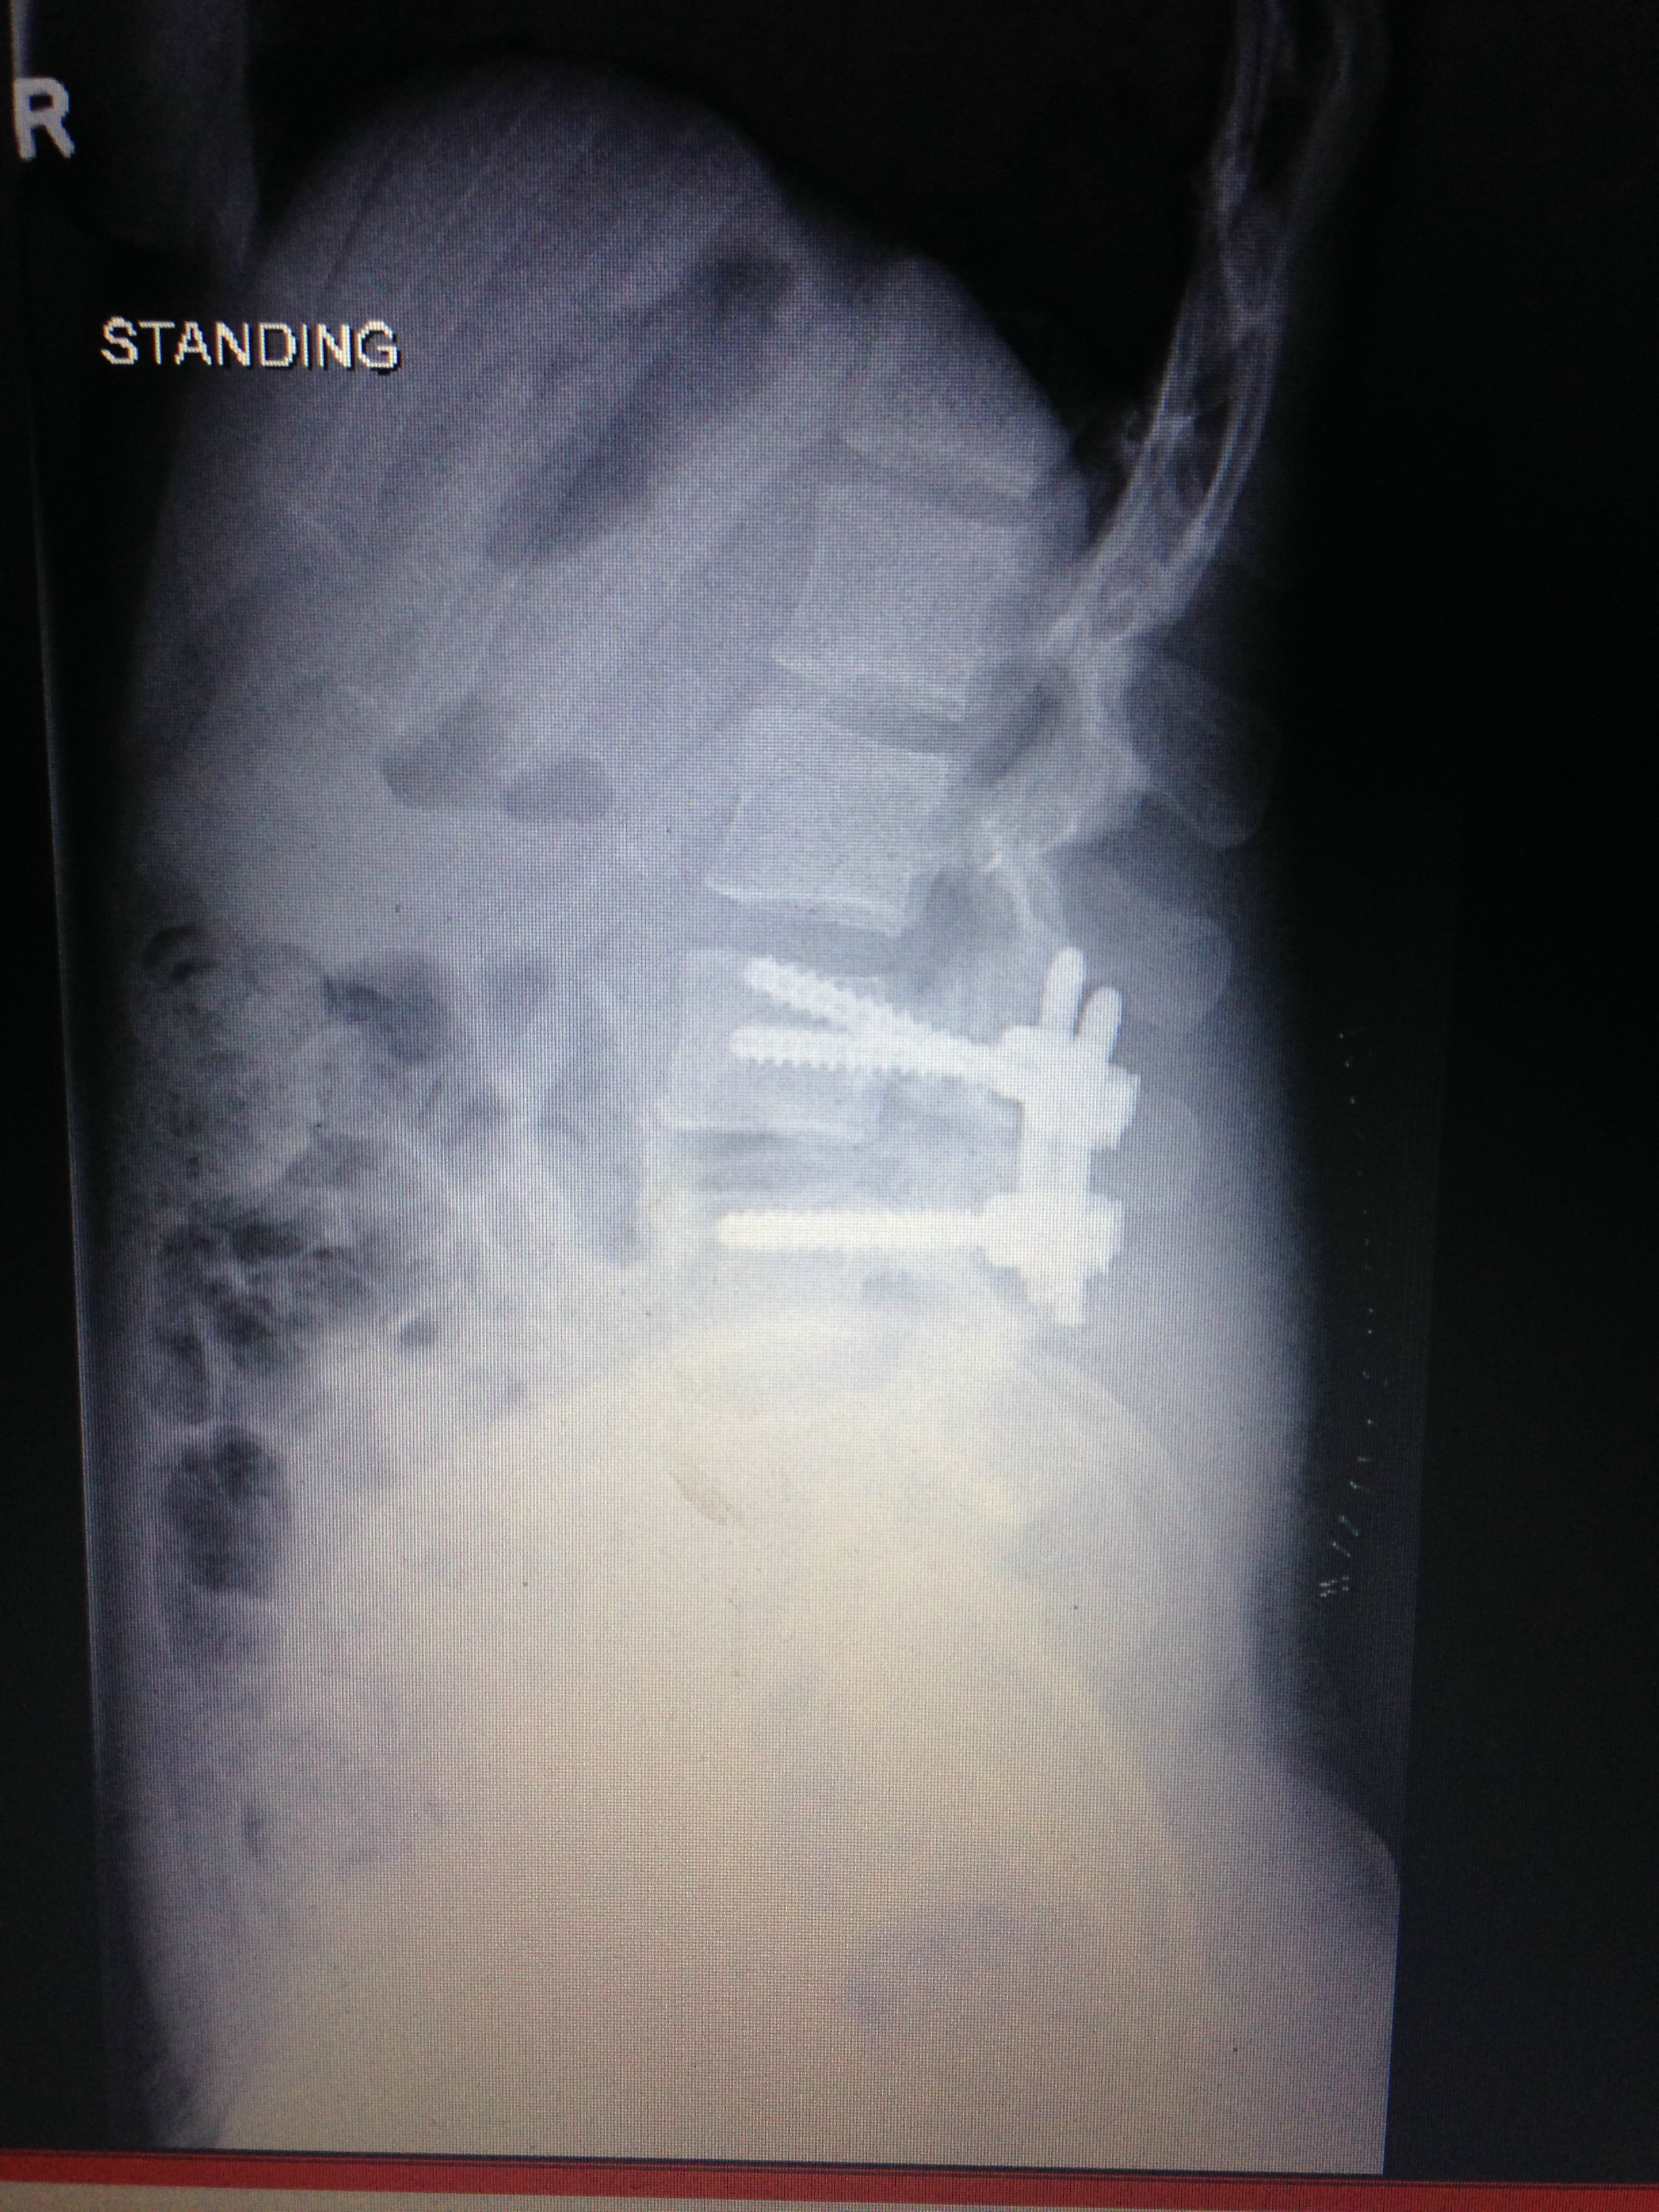

I demanded a CT scan and sure enough had two spinal breaks and the bone was swinging, so luckyily I did not become paralysed. They gave me a spinal fusion l3-4 with bone marrow, rods and screws. Six months later I learned how to walk again. I was gradually growing strong again, although I suffered left leg numbness post op, which never returned. I started Physio 10 months later and decided to travel as I felt I'd missed out.

My fiancé and I set off, but I had a fall in Calpe. I took myself to the hospital as my left foot went blue. That was April last year 2016 and I have slowly deteriorated since then. I told my surgeon I could still feel the bone moving in my spine, and he suggested to take the metal out. I demanded another scan, and it showed the fusion hadn't been successful, so taking the metal out wasn't an option.